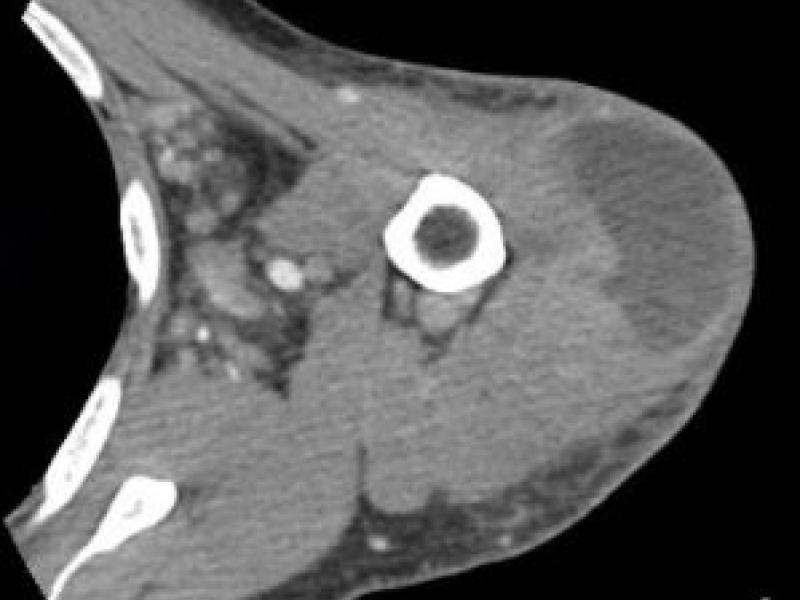

A 50 yo M w/ hx of HIV and IVDU presents to the ED w/